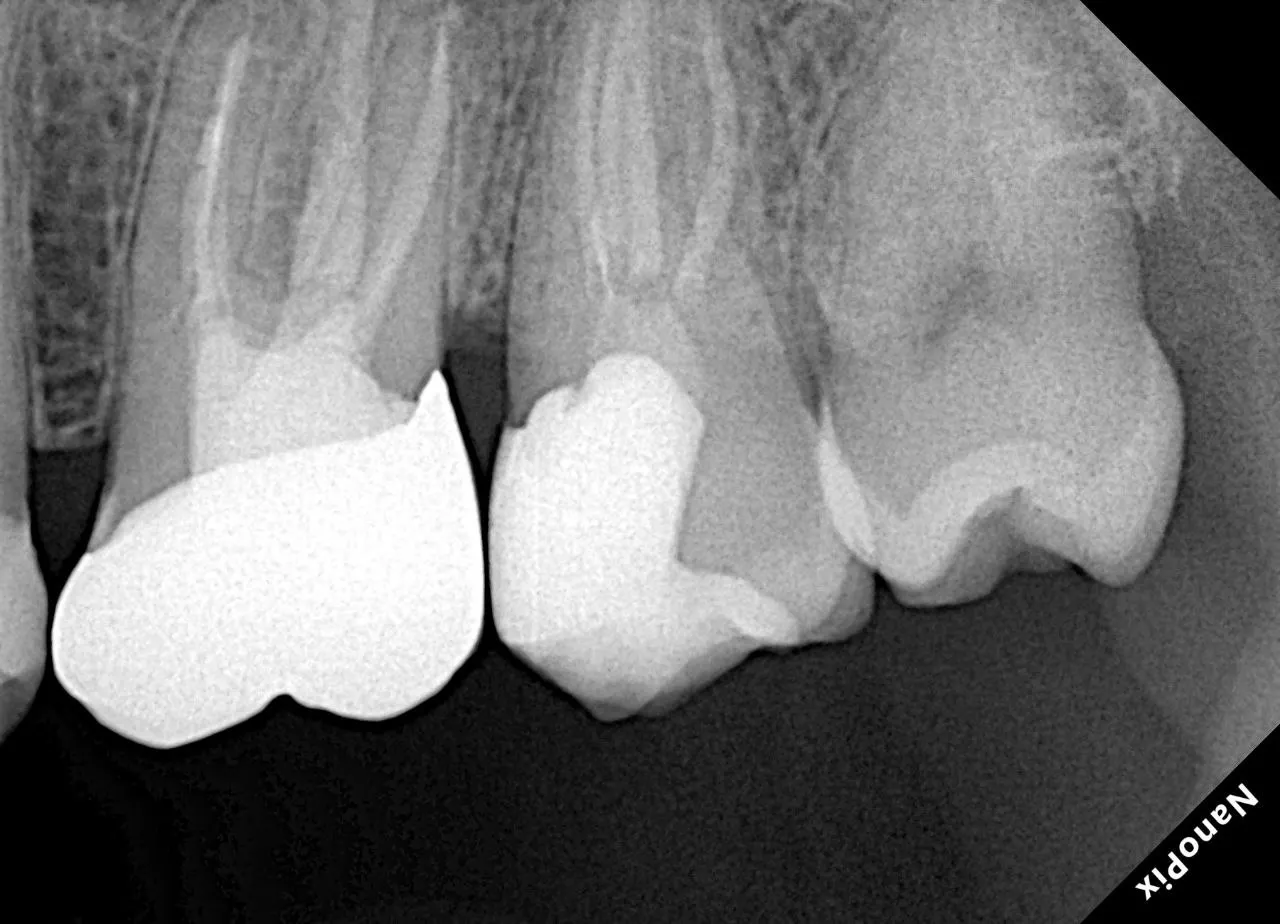

Профессионалы о нашей продукции

Мы тщательно следим за качеством нашей продукции и предлагаем только надежную технику, что без соменения производит впечатление на профессионалов в области эндонтии. Здесь вы можете увидеть те самые, искренние и настоящие отзывы наших клиентов.